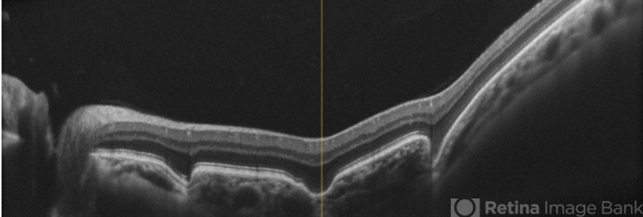

- optical coherence tomography (OCT), excavation, pachychoroid

- A 51-year-old female who reported low visual acuity on AO, worse in the OE. Fundoscopy of OE is observed color and brightness alteration in macular region. Focal concave-shaped chorioretinal anomaly in the foveal region and other two anomaly peripapilary and temporal to the fovea with a hyporreflective subretinal space distinguishing from each other.